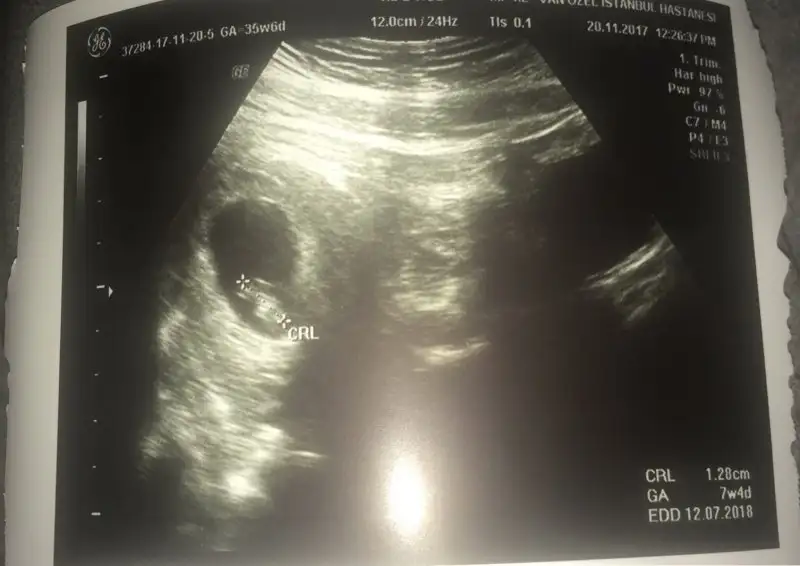

Canim benim oglum sagdaydi :) simdi gene sagda :) birde su var kese yuvarlaksa kiz fasulye gibiyse sekli erkek mis benim oglusumda fasulye gibiydi simdi yusyuvarlak acaba ne :) once saglik tabi ama insan icindeki minigin ne oldugunu merak ediyor

Canım ama bu kesenin sağ da veya solda olması değil kesenin içindeki bebeğin sağ ya da solda olması mesela kese sağ da bebek kesenin içinde sol taraftaysa erkek yazıyor

Bu arada Allahım bağışlasın evlatlarını canım. Bide benim ikisinde de ayrı ultrason resmi ekledim biri fasulye :) çarşamba nasıl olacak bakalım çok heycanlıyım

Eklentiler

• 0D36B26E-F23E-47E7-B70F-327633403338.webp

0D36B26E-F23E-47E7-B70F-327633403338.webp

18 KB · Görüntüleme: 88

• F8604ACB-9F5D-455D-AFAA-175391BB23B8.webp

F8604ACB-9F5D-455D-AFAA-175391BB23B8.webp

19,3 KB · Görüntüleme: 84